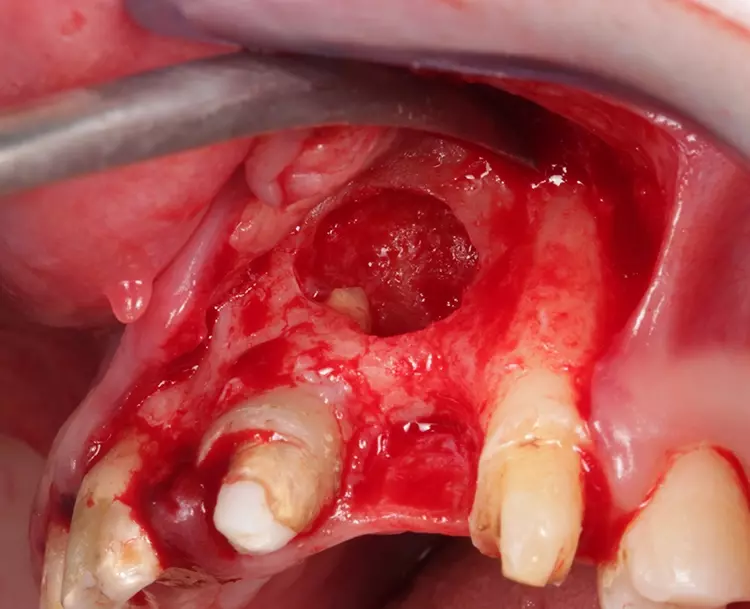

Im Rahmen der chirurgisch/konservierenden Vorbehandlung fanden folgende Eingriffe statt: Zystektomie 21 und Alveolarkamm-Rekonstruktion in regio 22 (Abb. 6), plastische Stiftaufbauten an den Zähnen 13, 12, 11, 21, 35, 33, 32, 42 und 43 nach vorangegangener endodontischer Revision und Wurzelspitzenresektionen bei Nichtausheilung im Apexbereich; aus finanziellen und strategischen Überlegungen Entfernung der Zähne 17 und 47 aufgrund diffuser Beschwerden (manchmal dumpf, leichter Druck, kälteempfindlich „je nach Wetterlage“) und infauster Prognose. Die Alternativtherapien wurden mit der Patientin ausführlich besprochen und abgewogen. Des Weiteren wurden eine Weichgewebeaugmentation der Oberkieferfront in regio 22 vorgenommen sowie eine Verdickung des Weichgewebes mit Bindegewebetransplantaten in Tunnelierungstechnik unter zusätzlichem Einsatz von Schmelzmatrixprotein und eine Lippenbandexzision in regio 31/41 durchgeführt (Abb. 7).

Die Implantation (zweizeitiges Vorgehen) fand an den Positionen 036, 045 und 031 statt (Replace Select Tapered RP jeweils 8 mm und Nobel Active 3.0 im UK-Frontzahnbereich Länge 10 mm, Nobel Biocare) [21]. Zeitgleich wurde nach Implantatverschluss mit Deckschrauben eine ortständige Augmentation mit Knochenersatzmaterial (DBBM, Bio Oss®, Geistlich) durchgeführt, mit Kollagenmembran (BioGide®, Geistlich) stabilisiert und anschließend mit 5.0er Naht verschlossen.

Im nächsten Schritt erfolgte die Insertion eines Einzelzahnimplantats in regio 22. Nach erfolgter Einheilphase von 6 Monaten [21] wurde für die definitive Versorgung eine verschraubte Implantateinzelkrone (Creapresskäppchen und feldspatkeramische Verblendung, Creation Willi Geller, KLEMA Dentalprodukte, Österreich) auf einem geklebten Titanabutment (A3 Dental) (Multilink Hybrid-Abutment, Ivoclar) gewählt.

Zusätzlich erfolgte aufgrund einer Kronen-/Wurzelfraktur an Zahn 42 ein Ersatz per Sofortimplantation in zweizeitiger Vorgehensweise mit einem Nobel Active®-Implantat (3.0, 10 mm, Nobel Biocare). Für die Einheilphase erfolgte der Implantverschluss mit einer Deckschraube.

Im Zuge der Implantation wurde auch eine Weichgewebeaugmentation mit anschließendem primärem Wundverschluss durchgeführt. Zur prä- und postoperativen Antibiose wurde Augmentin 625 mg für 5 Tage rezeptiert und administriert. Die Schmerzmedikation stand nach Bedarf zur Verfügung.